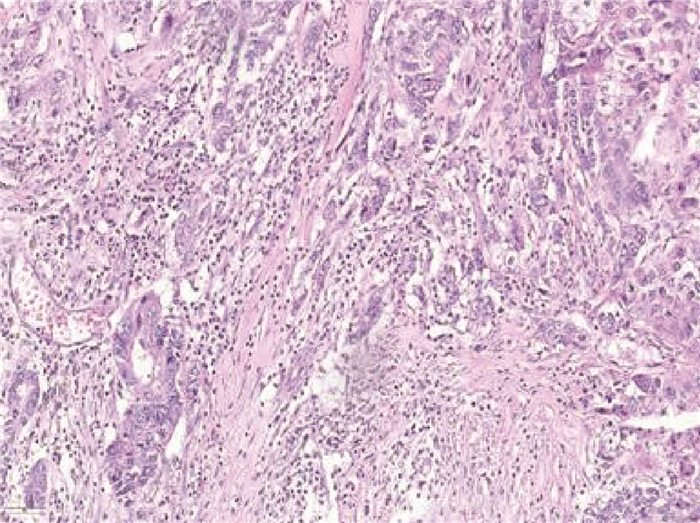

Primary liver cancer with prostate metastasis: A case report